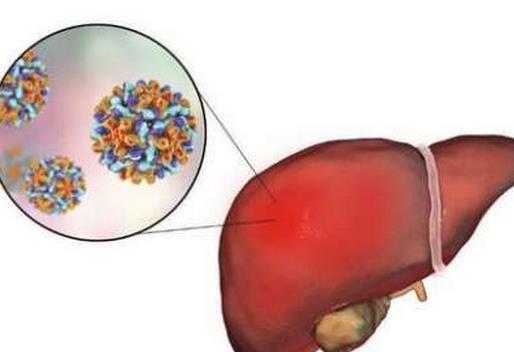

2ĪóĘ╬░®

Ę╬░®╩Ū░l▓Ī┬╩║═╦└═÷┬╩ūŅ┐ņĄ─░®░Yų«ę╗Ż¼ļm╚╗╦³Ą─▓Īę“─┐Ū░▀Ć▓╗┤_Č©Ż¼Ą½┐╔ęį┐ŽČ©Ą─╩Ū╬³¤¤┼c╗╝Ę╬░®Ą─ĻPŽĄśO×ķ├▄ŪąĪŻčąŠ┐▒Ē├„Ż¼╬³¤¤Ą─╚╦╗╝Ę╬░®╩Ū▓╗╬³¤¤Ą─20▒ČŻ¼Č°Ę╬░®ūŅų„ꬥ─ų╬»¤ĘĮĘ©Š═╩Ū╗»»¤ĪŻ